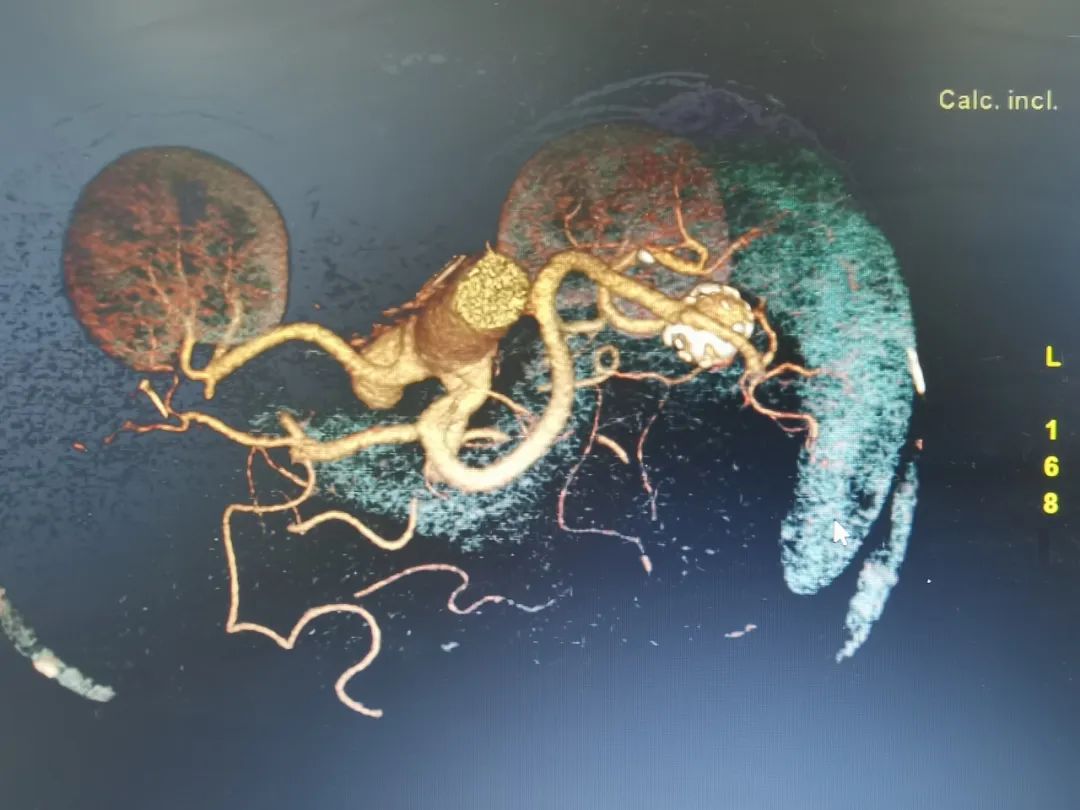

经过完善的术前评估,普外科邀请集团普外医疗中心血管外科桂锐主任、胡玉东主任,仅在股动脉做一2cm小切口,通过一根导丝,精准定位瘤体位置,将弹簧圈置入瘤腔,顺利完成手术。

“患者的脾动脉瘤直径较大,属于囊状动脉瘤,瘤体向动脉一侧偏心性扩张,这类口袋状的动脉瘤,破裂的风险更高,占总数的75%。患者发现及时,手术顺利,很幸运。”胡玉东主任说。